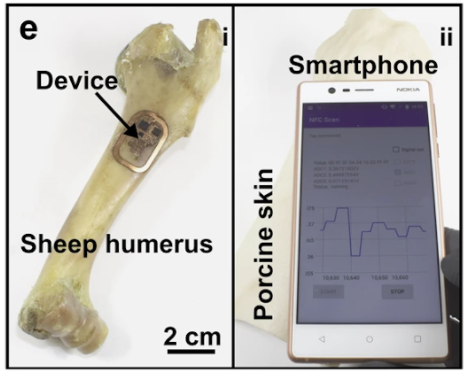

It isn’t very practical to cut through the surrounding tissue every time you want to run a test on bones. The authors behind the recent study, published in Nature Communications, took a different and more humane approach: implanting a device on the surface of the bone that can run the tests for you. This still requires cutting through the surrounding tissue, but only once. Still, designing a computer that can live on the surface of a bone comes with some challenges.

As you move, your muscles slide across your bones. There is very little space between these two tissues. So, the researchers designed the device to be as thin as a piece of paper (with a length and width roughly the size of the first knuckle on your index finger). This ensured that the device was thin enough to avoid irritating surrounding tissue or become dislodged during muscle movement and also be flexible enough to contort to the bone.

Muscle movement isn’t the only factor that could cause the device to become dislodged. Bone is in a constant state of remodeling, with some cells destroying old bone tissue, while other cells are creating new bone tissue. Due to this, traditional attachment methods would gradually lose adhesion. To address this, study co-author and biomedical engineer John Szivek developed an adhesive that contains calcium particles similar to bone.

With this design, the device is able to form a permanent bond to the bone and take measurements. This opens the doors for studying bone diseases that develop over years, such as Paget’s diseases, which results in fragile, misshapen bones. But how can the device stay powered for years or even decades?

The tiny device does not have a long-lasting battery. In fact, it has no battery at all. The author ditched it to keep the size down. Instead, the team utilized the same technology used in smartphones for contactless payments: near-field communication (NFC), which solved their power problem and also allowed them to communicate with the device.

Designing a device that can live on the bone for extended periods with the capacity for wireless power and communication is an impressive feat of engineering. But how does it make it easier to study and protect bone health? The device is also equipped with components capable of measuring bone strength and healing and stimulating bone growth.

Imagine you fracture your femur and your physician implants this device to stimulate healing and monitor the temperature. When the temperature starts to get too high, light stimulation could be reduced. And since the device utilizes the same NFC common to cell phones, individuals could monitor and intervene without visiting a physician.